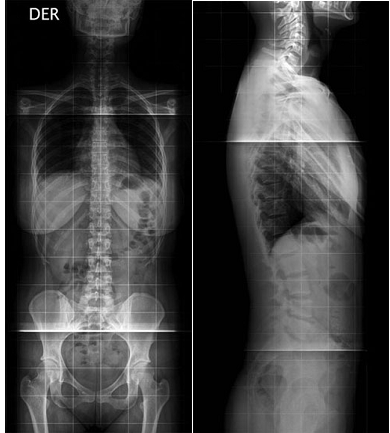

ESCOLIOSISLa escoliosis propiamente es la desviación lateral de la columna vertebral, asociada a rotación de los cuerpos vertebrales y alteración estructural de ellos. El término escoliosis proviene de una palabra griega que significa “torcido”. Se observa con frecuencia entre los 10 y 14 años y se inicia después de los 8 años, con un índice de 6 a 1 en las mujeres. Las personas pueden tener escoliosis a cualquier edad. El tipo más común es la escoliosis idiopática, o de origen desconocido, entre los niños de 10 a 12 años y al inicio de la adolescencia. Es a esta edad que los niños crecen con rapidez. Las niñas tienen una mayor predisposición a este tipo de escoliosis que los varones.

TRATAMIENTOEl tratamiento se inicia con la observación, ya que hay un importante número de casos que sólo hay que controlar y no requieren nunca tratamiento ortopédico. En general, a estos pacientes se les agrega ejercicios por medio de fisioterapia para mantener la columna flexible y mejorar la potencia muscular, abdominal y paravertebral. El siguiente grado en el tratamiento es el uso de corsé (el más empleado es el corsé de Milwaukee).

Está destinado a aquellos pacientes que están fuera del alcance ortopédico. Es decir pacientes con curvas sobre 45º, rígidas, mayores de 14 años, Risser 4, o que las curvas hayan aumentado dentro del corsé. El índice de Risser para estimación de maduración ósea, evalúa el grado de aparición del núcleo de osificación de la cresta ilíaca y su fusión al ala ilíaca, como se observa en la tabla. El grado de madurez ósea es otro de los factores pronósticos de la escoliosis idiopática, existiendo una mayor progresión de la curva en niños con un grado de Risser 0 ó 1, que en grados 2 a 5. La ventaja de utilizar este método es que las alas ilíacas están frecuentemente incluidas en la radiografía, por lo que sería innecesario contar con radiografías adicionales para la estimación de edad ósea(4). Indice de Risser

También requieren tratamiento quirúrgico para su corrección, aquellos pacientes que alcanzaron su maduración ósea y presentan curvas sobre 45º. El objetivo del tratamiento quirúrgico es estabilizar la columna ya que, de lo contrario, las curvas seguirían progresando y haciéndose cada vez más rígidas. El tratamiento quirúrgico pretende básicamente disminuir la magnitud de las curvas y mejorar las deformaciones estéticas. Esto se logra a través de la fusión de la zona de columna comprometida, luego de la corrección de las curvas con instrumental de distracción, compresión y desrotación de los cuerpos vertebrales, con sistemas de barras y ganchos o sistemas de Luque.